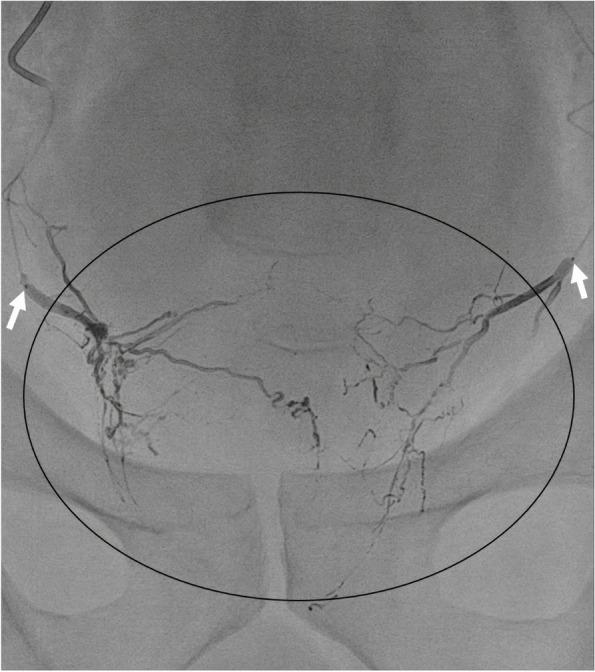

Ten consecutive patients treated by PAE with EVOH for the presence of disabling benign prostatic hyperplasia (BPH)-related lower urinary tract symptoms (LUTS) between June 22 and January 2023 were included in this prospective study. The inclusion criteria were as follows: LUTS attributed to BPH, LUTS duration ≥ 6 months, failure to respond to standard pharmacotherapy, IPSS > 18 or QoL score > 2, and prostate volume > 40 mL. Embolization was performed under general anaesthesia. According to established techniques, a microcatheter was positioned bilaterally within the feeding arteries, and EVOH was injected slowly under X-ray control. Unenhanced pelvic computed tomography scans were carried out before and after embolization to assess the NTE. The safety of the prostatic embolization procedure with EVOH was assessed by collecting adverse effects over 3 months of evaluation that included the International Prostate Symptom Score (IPSS) and quality of life (QoL) score.-up evaluations, occurring at 3, 6, and 12months, included International Prostate Symptom Score. Bilateral PAE was technically successful in 9 patients, and unilateral injection was performed in one patient. The postoperative scanner showed a distribution of the embolization material in the two lobes of the prostate in all patients. The procedure time varied from 120 to 150 (mean: 132) minutes. Eight out of 10 patients developed pollakiuria within 24 h; none of the patients had postoperative pain. Two patients required catheterization for postoperative urinary retention. Catheters were removed successfully at the end of the first day for one of these patients and on the tenth day for the other. At the 3-month follow-up, patients showed significant improvement in the International Prostate Symptom Score (n = 10; mean = -11,5; P < 0.01) and quality of life score (n = 10; mean = -3,40; P < 0.01). Only one patient presented one asymptomatic muscular NTE.

PAE with EVOH is safe, effective, and associated with few NTEs and no postoperative pain. Prospective comparative studies with longer follow-ups are warranted.